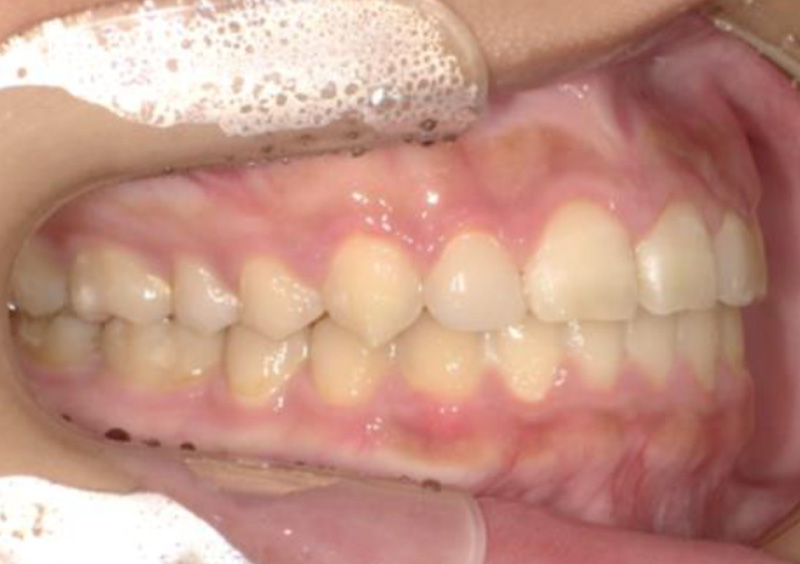

大人の矯正治療 歯に隙間がある(空隙歯列) 2025.10.24 【マルチブラケット矯正】隙間が気になる 治療前 治療後 担当医 一瀬 悠依華 先生 主訴 隙間が気になる。 期間 2年半 費用 65万円 治療内容 マルチブラケット装置 治療に伴うリスク 歯根吸収、歯肉退縮 関連症例